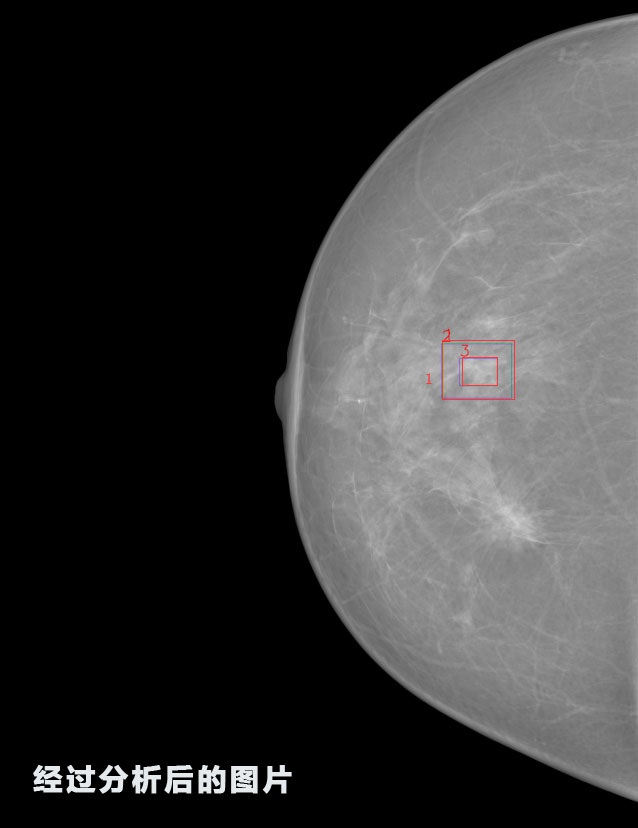

英特健康AI深度學習醫(yī)療圖像識別系統(tǒng)案例_乳腺

識別報告:

1.發(fā)現(xiàn)良性鈣化,可能性為19.88%---位置框指數(shù):[1796.0867 1359.8237 2058.1372 1582.5334]

2.發(fā)現(xiàn)惡意鈣化的可能性為15.18%---位置框指數(shù):[1789.4733 1365.9951 2063.7698 1576.0613]

3.發(fā)現(xiàn)惡意鈣化的可能性為12.45%---位于框指數(shù):[1859.3987 1422.3184 2006.5494 1528.2698]